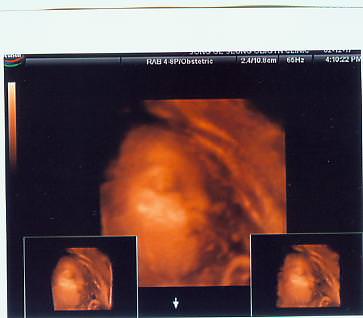

우리 깜코랑 찍은 사진...

깜코 몸무게가 궁금할 정도로 우량아입니다.. ~.~::